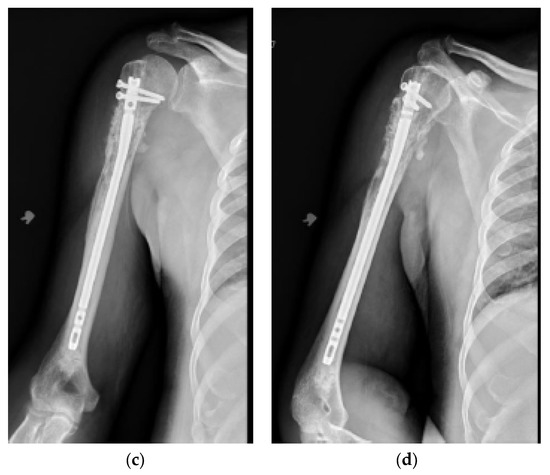

Figure 3.

(a) AP and (b) oblique left humerus radiographs of a 47-year-old female with mixed lytic sclerotic lesion in the proximal meta-diaphyseal region, with a pathologic fracture and periosteal reaction in a patient with established metastatic breast cancer. This was treated by an uncemented IMN, with three proximal locking screws and one distal screw, as shown in (c) AP and (d) oblique humerus radiographs. No cement was used, as there was enough proximal and distal bone to support the nail and the inter-locking screws, and some healing changes were already evident.